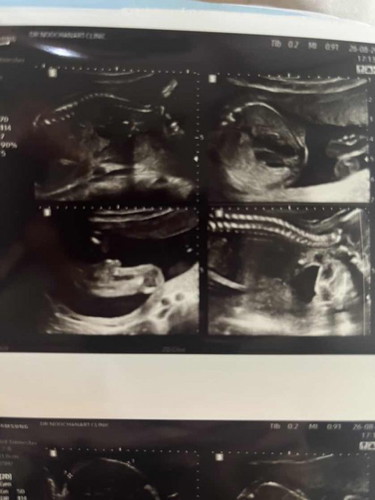

รบกวนแม่ๆช่วยดูหน่อยค่ะว่าชายหรือหญิง

แม่ๆ ช่วยดูหน่อยค่ะ ว่าได้ ลูกชายรึลูกสาว 🫣🤭 ขอบคุณมากๆค่ะ ❣️❣️

ไม่เห็นนะคะ แต่คิดว่าผญ เพราะผชจะเห็นจุ๊ดจู๋ชี้เลยค่ะ